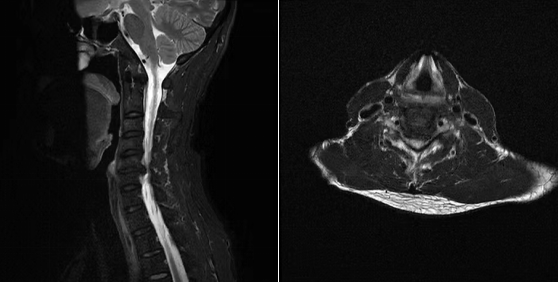

▲术前MRI提示颈5/6椎间盘突出

同节段脊髓变性,椎管狭窄